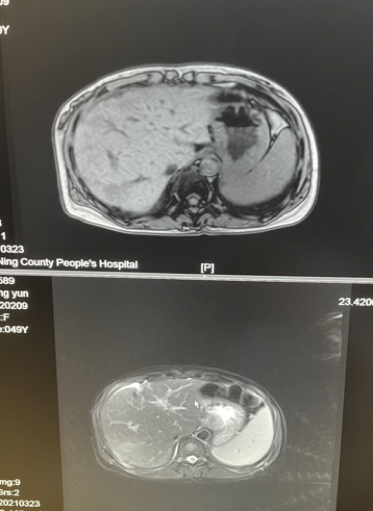

2021年3月23日上腹部MR示:肝CA术后,下腔静脉肝内端狭窄,肝中静脉及肝左静脉未见明确显示(图4)。AFP 228.68ng/ml, 余瘤标正常。

图4.2021年3月23日上腹部MR

2021年6月18日复查MR示(图5),增强扫描右肝叶病灶无强化,延迟扫描肝右叶弥漫性不均匀强化。肿瘤标志物AFP为338.35ng/ml,较前上升。

图5.2021年6月18日复查MR